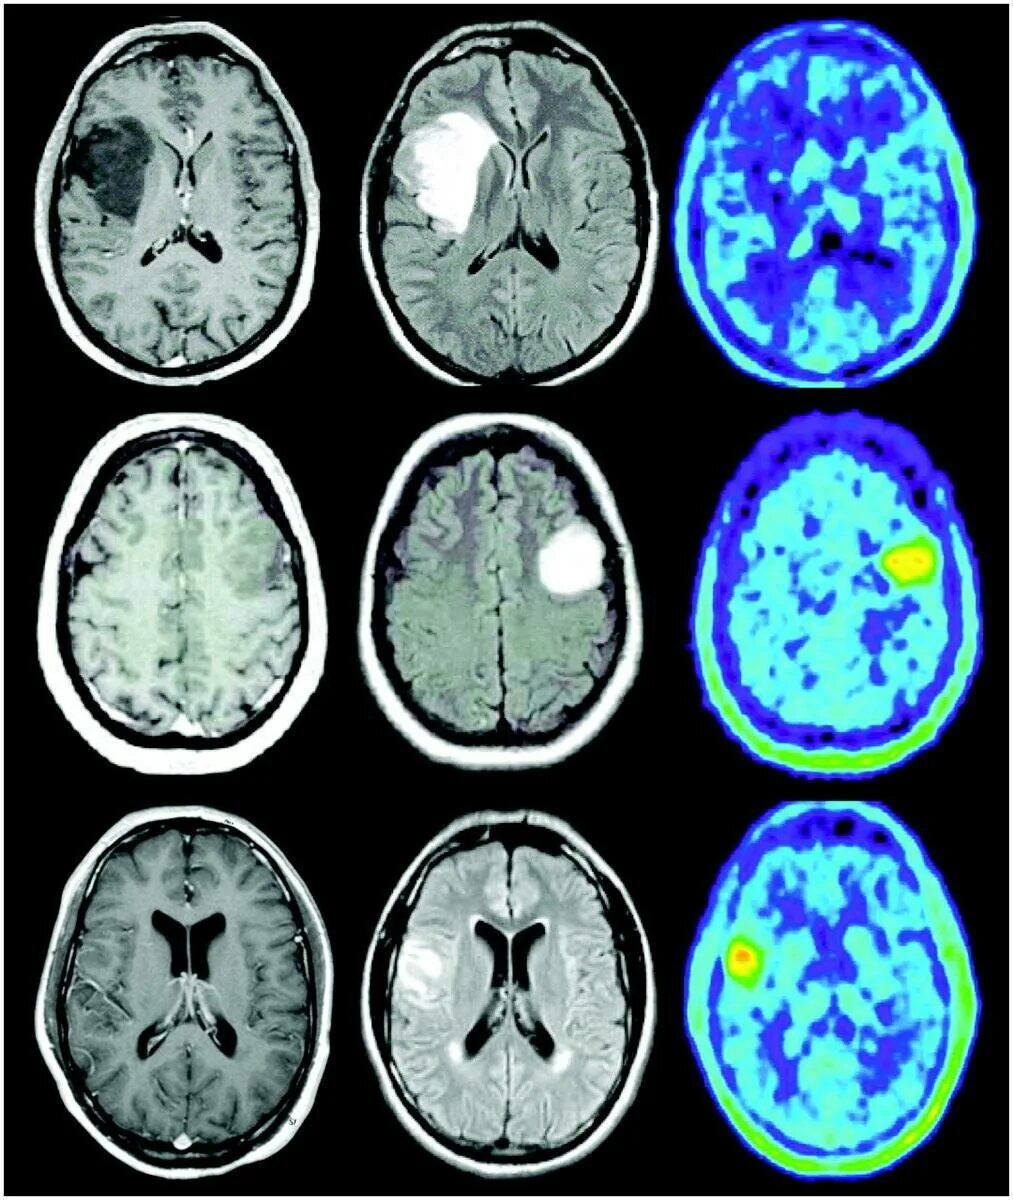

Стадии рака мозга симптомы